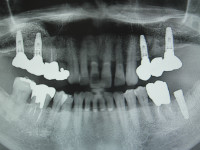

今日のインプラントオペは右上臼歯部です。

この部位は上顎洞底からの骨の厚みが4ミリ程しかありませんでしたので、先にサイナスリフトを行い同時法でインプラントを埋入いたしました。

最後の2枚は定期チェックにいらっしゃった患者様の画像です、ご了解の上でアップさせて頂きました、サイナス後、9年ほど経過しておりますがしっかり噛み込めており問題なしです。